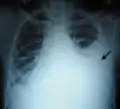

پلورال افیوژن وسیع در سمت چپ قفسهٔ سینه (بخش سفید رنگ) در بیمار مبتلا به سرطان ریه.

پلورال افیوژن وسیع در مردی از اهالی جنوب هندوستان که بعداً مشخص شد هموتوراکس بودهاست.